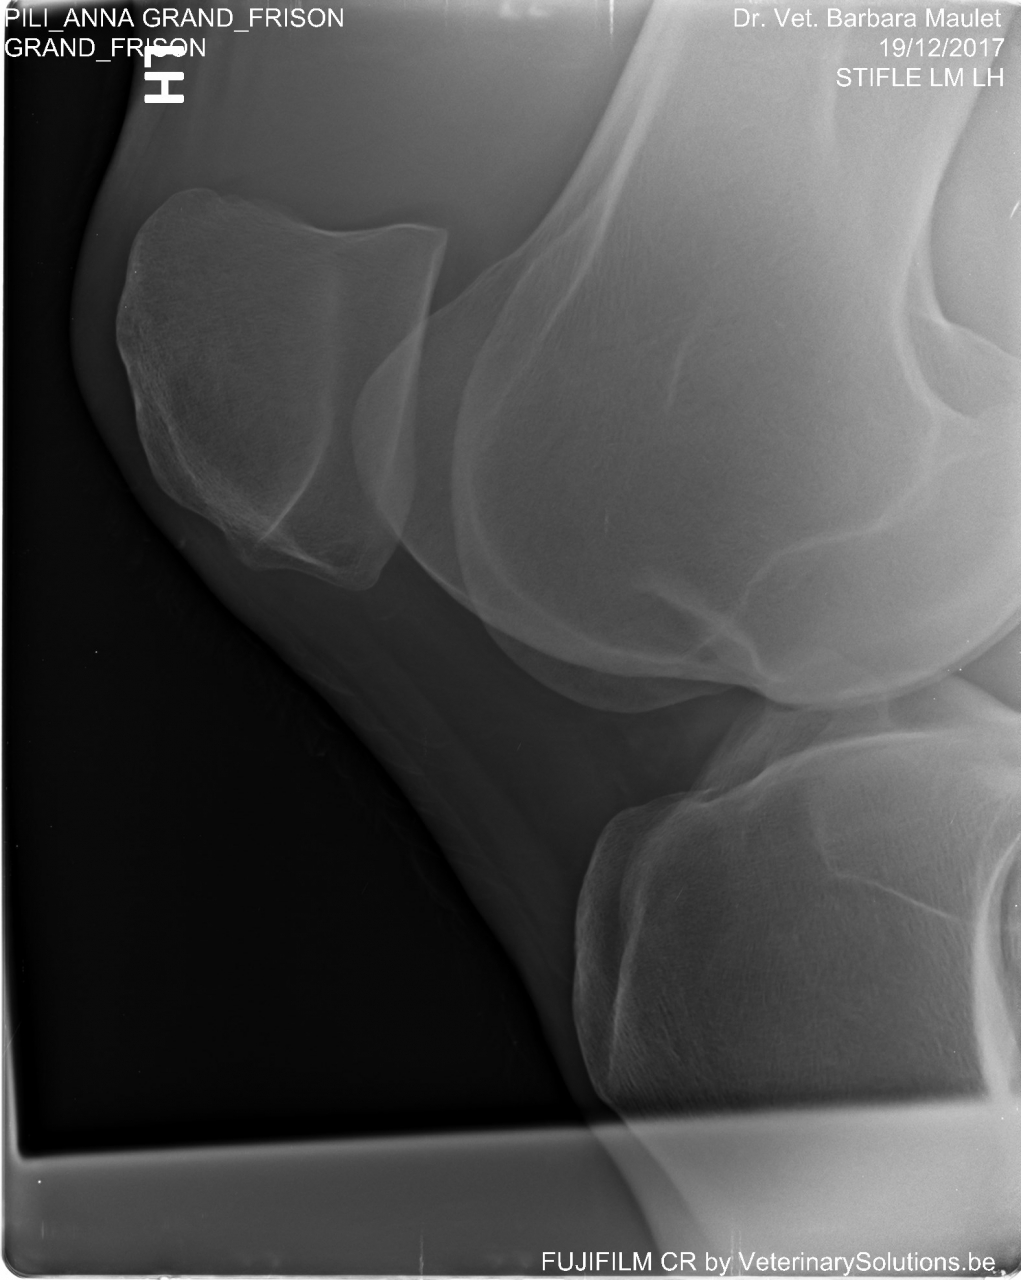

DéconnectéDire merci | pour ceux qui savent lire une radio voici ce que ça donne. rotule totalement déplacée c'est pas un accrochement mais bien une luxation (moi et les termes médicaux); pas moyen de remettre les ligaments. La bonne nouvelle c'est qu'il n'y a ni arthrose ni fracture. Les cheval n'est pas en grosse douleur au repos. Il peut encore profiter de la vie au calme jusqu'à ce que la douleur permanente s'installe. ![]() |